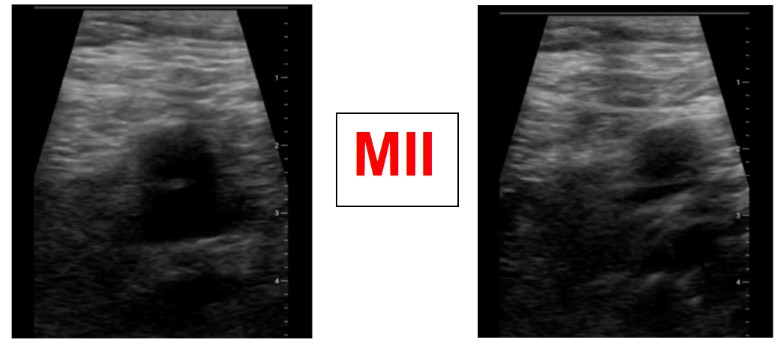

En la exploración se aprecia MID con un evidente mayor tamaño que el izquierdo, más enrojecido y con edema que deja fóvea hasta mitad de muslo (3 puntos en la escala de Wells).

Ante la sospecha de Trombosis venosa profunda realizamos ecografía de compresión venosa de miembros inferiores detectando la falta de colapsabilidad de la femoral común y femoral superficial del miembro inferior derecho, cosa que no pasaba en el izquierdo.